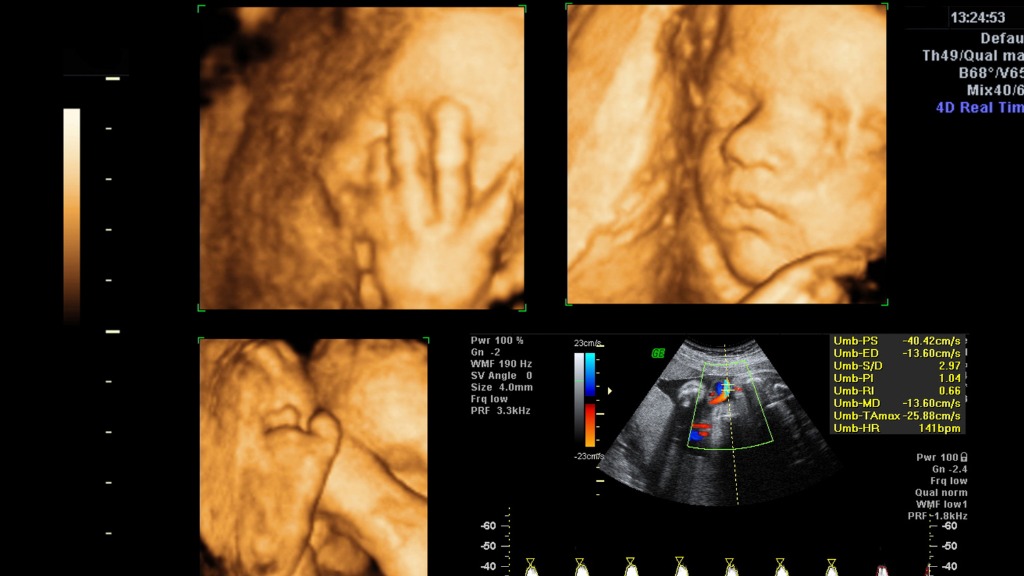

Siêu âm 4D là bước tiến vượt bậc trong lĩnh vực chẩn đoán hình ảnh sản khoa. Khác với siêu âm 2D truyền thống chỉ cung cấp hình ảnh mặt cắt đen trắng, siêu âm 4D cho phép tái tạo hình ảnh thai nhi theo không gian ba chiều và hiển thị chuyển động theo thời gian thực.

- Quan sát hình thái bên ngoài của thai nhi một cách trực quan.

- Đánh giá cấu trúc khuôn mặt, tay chân, cột sống, thành bụng.

- Hỗ trợ phát hiện sớm hoặc muộn một số dị tật bẩm sinh.

- Theo dõi tình trạng nước ối, bánh nhau và tư thế thai.

Bên cạnh giá trị chẩn đoán, siêu âm 4D còn mang ý nghĩa tinh thần lớn đối với gia đình. Việc nhìn thấy cử động, biểu cảm của con ngay từ trong bụng mẹ giúp tăng sự gắn kết cảm xúc, đồng thời giúp cha mẹ yên tâm hơn về sự phát triển của thai nhi.

Hình ảnh 4D ở giai đoạn này thường cho thấy rõ nét khuôn mặt và biểu cảm của bé. Tuy nhiên, do thai đã lớn hơn, không gian trong tử cung hạn chế nên đôi khi hình ảnh không còn bao quát toàn bộ cơ thể như giai đoạn giữa thai kỳ.